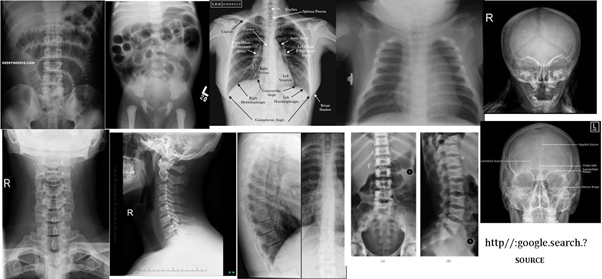

This Medical Imaging Science Discipline Course is a continuation of the MRI Series in which the students develop their radiographic techniques in radiation imaging examinations. The students are introduced to chest, abdomen, head and spine radiography. Radiation Safety Practice and Image Quality Factors are further learnt in enhancing the student's competencies towards conventional radiography.

Medical Radiation Imaging II is a second year course under the Bachelor of Medical Imaging Science program and it introduces the undergraduates to imaging sciences in radiography, specifically the imaging principles, techniques and skills, and radiation protection involved in radiographic procedures and examinations of the axial region of the human anatomy. It is a continuation from MRI I and it covers Chest, Abdomen, Spine and Skull Radiography. Furthermore, it will also help the undergraduate to develop and enhance their written and oral communication (English). The course is significant as it establishes vital connections that enable students to complete the year of study through team effort and correlating with other courses for clinical applications.